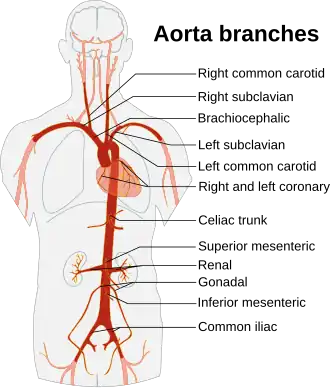

Branches of the aorta | |

| Branches | Ascending aorta:

Arch of aorta (supra-aortic vessels): Descending aorta, thoracic part:

Descending aorta, abdominal part:

Terminal branches: |

The aortic arch has three major branches: from proximal to distal, they are the brachiocephalic trunk, the left common carotid artery, and the left subclavian artery. The brachiocephalic trunk supplies the right side of the head and neck as well as the right arm and chest wall, while the latter two together supply the left side of the same regions.

The thoracic aorta gives rise to the intercostal and subcostal arteries, as well as to the superior and inferior left bronchial arteries and variable branches to the esophagus, mediastinum, and pericardium. Its lowest pair of branches are the superior phrenic arteries, which supply the diaphragm, and the subcostal arteries for the twelfth rib.[9]: 195

The abdominal aorta begins at the aortic hiatus of the diaphragm at the level of the twelfth thoracic vertebra.[10] It gives rise to lumbar and musculophrenic arteries, renal and middle suprarenal arteries, and visceral arteries (the celiac trunk, the superior mesenteric artery and the inferior mesenteric artery). It ends in a bifurcation into the left and right common iliac arteries. At the point of the bifurcation, there also springs a smaller branch, the median sacral artery.[9]: 331

The aorta supplies all of the systemic circulation, which means that the entire body, except for the respiratory zone of the lung, receives its blood from the aorta. Broadly speaking, branches from the ascending aorta supply the heart; branches from the aortic arch supply the head, neck, and arms; branches from the thoracic descending aorta supply the chest (excluding the heart and the respiratory zone of the lung); and branches from the abdominal aorta supply the abdomen. The pelvis and legs get their blood from the common iliac arteries.